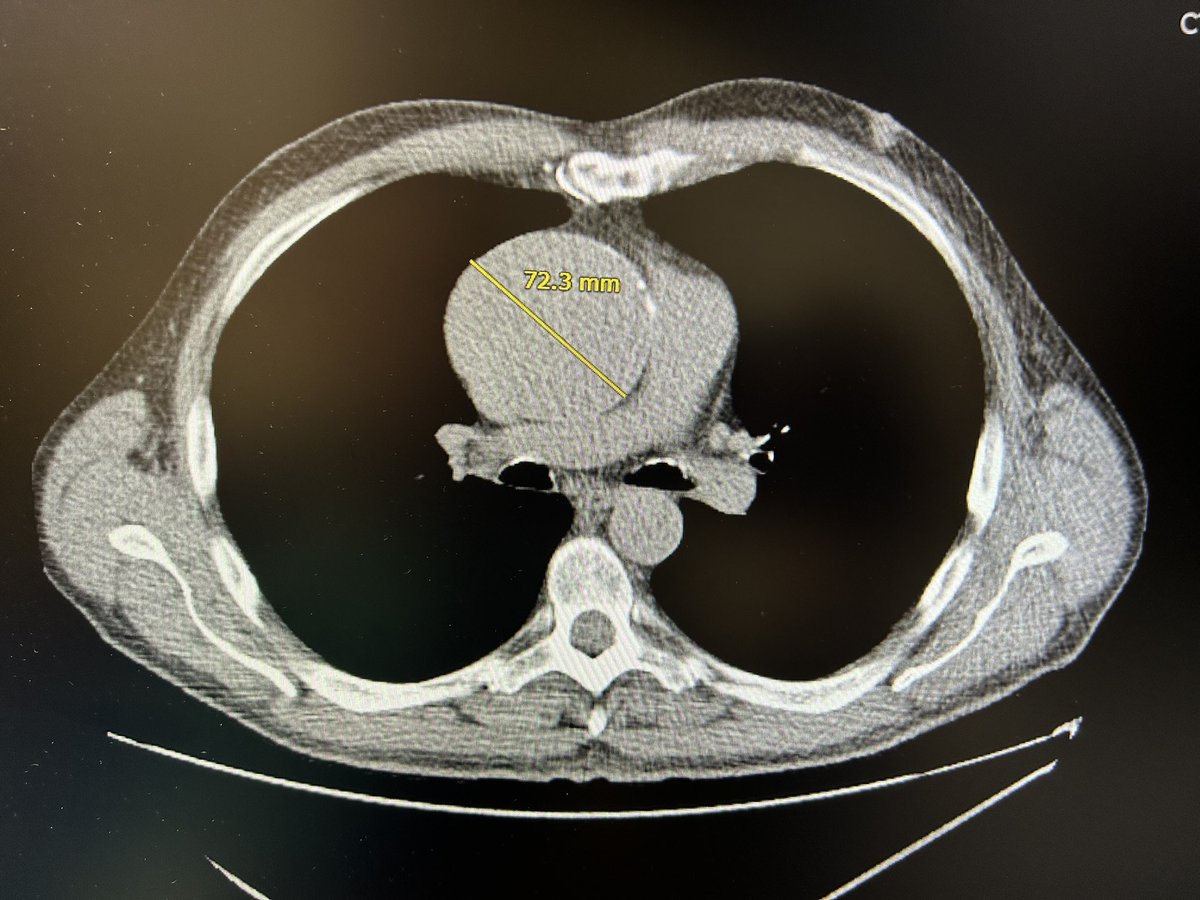

Anat and Dr. Shmuel Harlap donated 180 million USD to Rabin Medical Center – Beilinson Hospital. The historic donation is earmarked for the construction of a new Heart and Brain Center. The Harlap family announced that the new facility will be named “The Tower of Hope”, symbolizing their desire to help healing divisions within Israeli society.